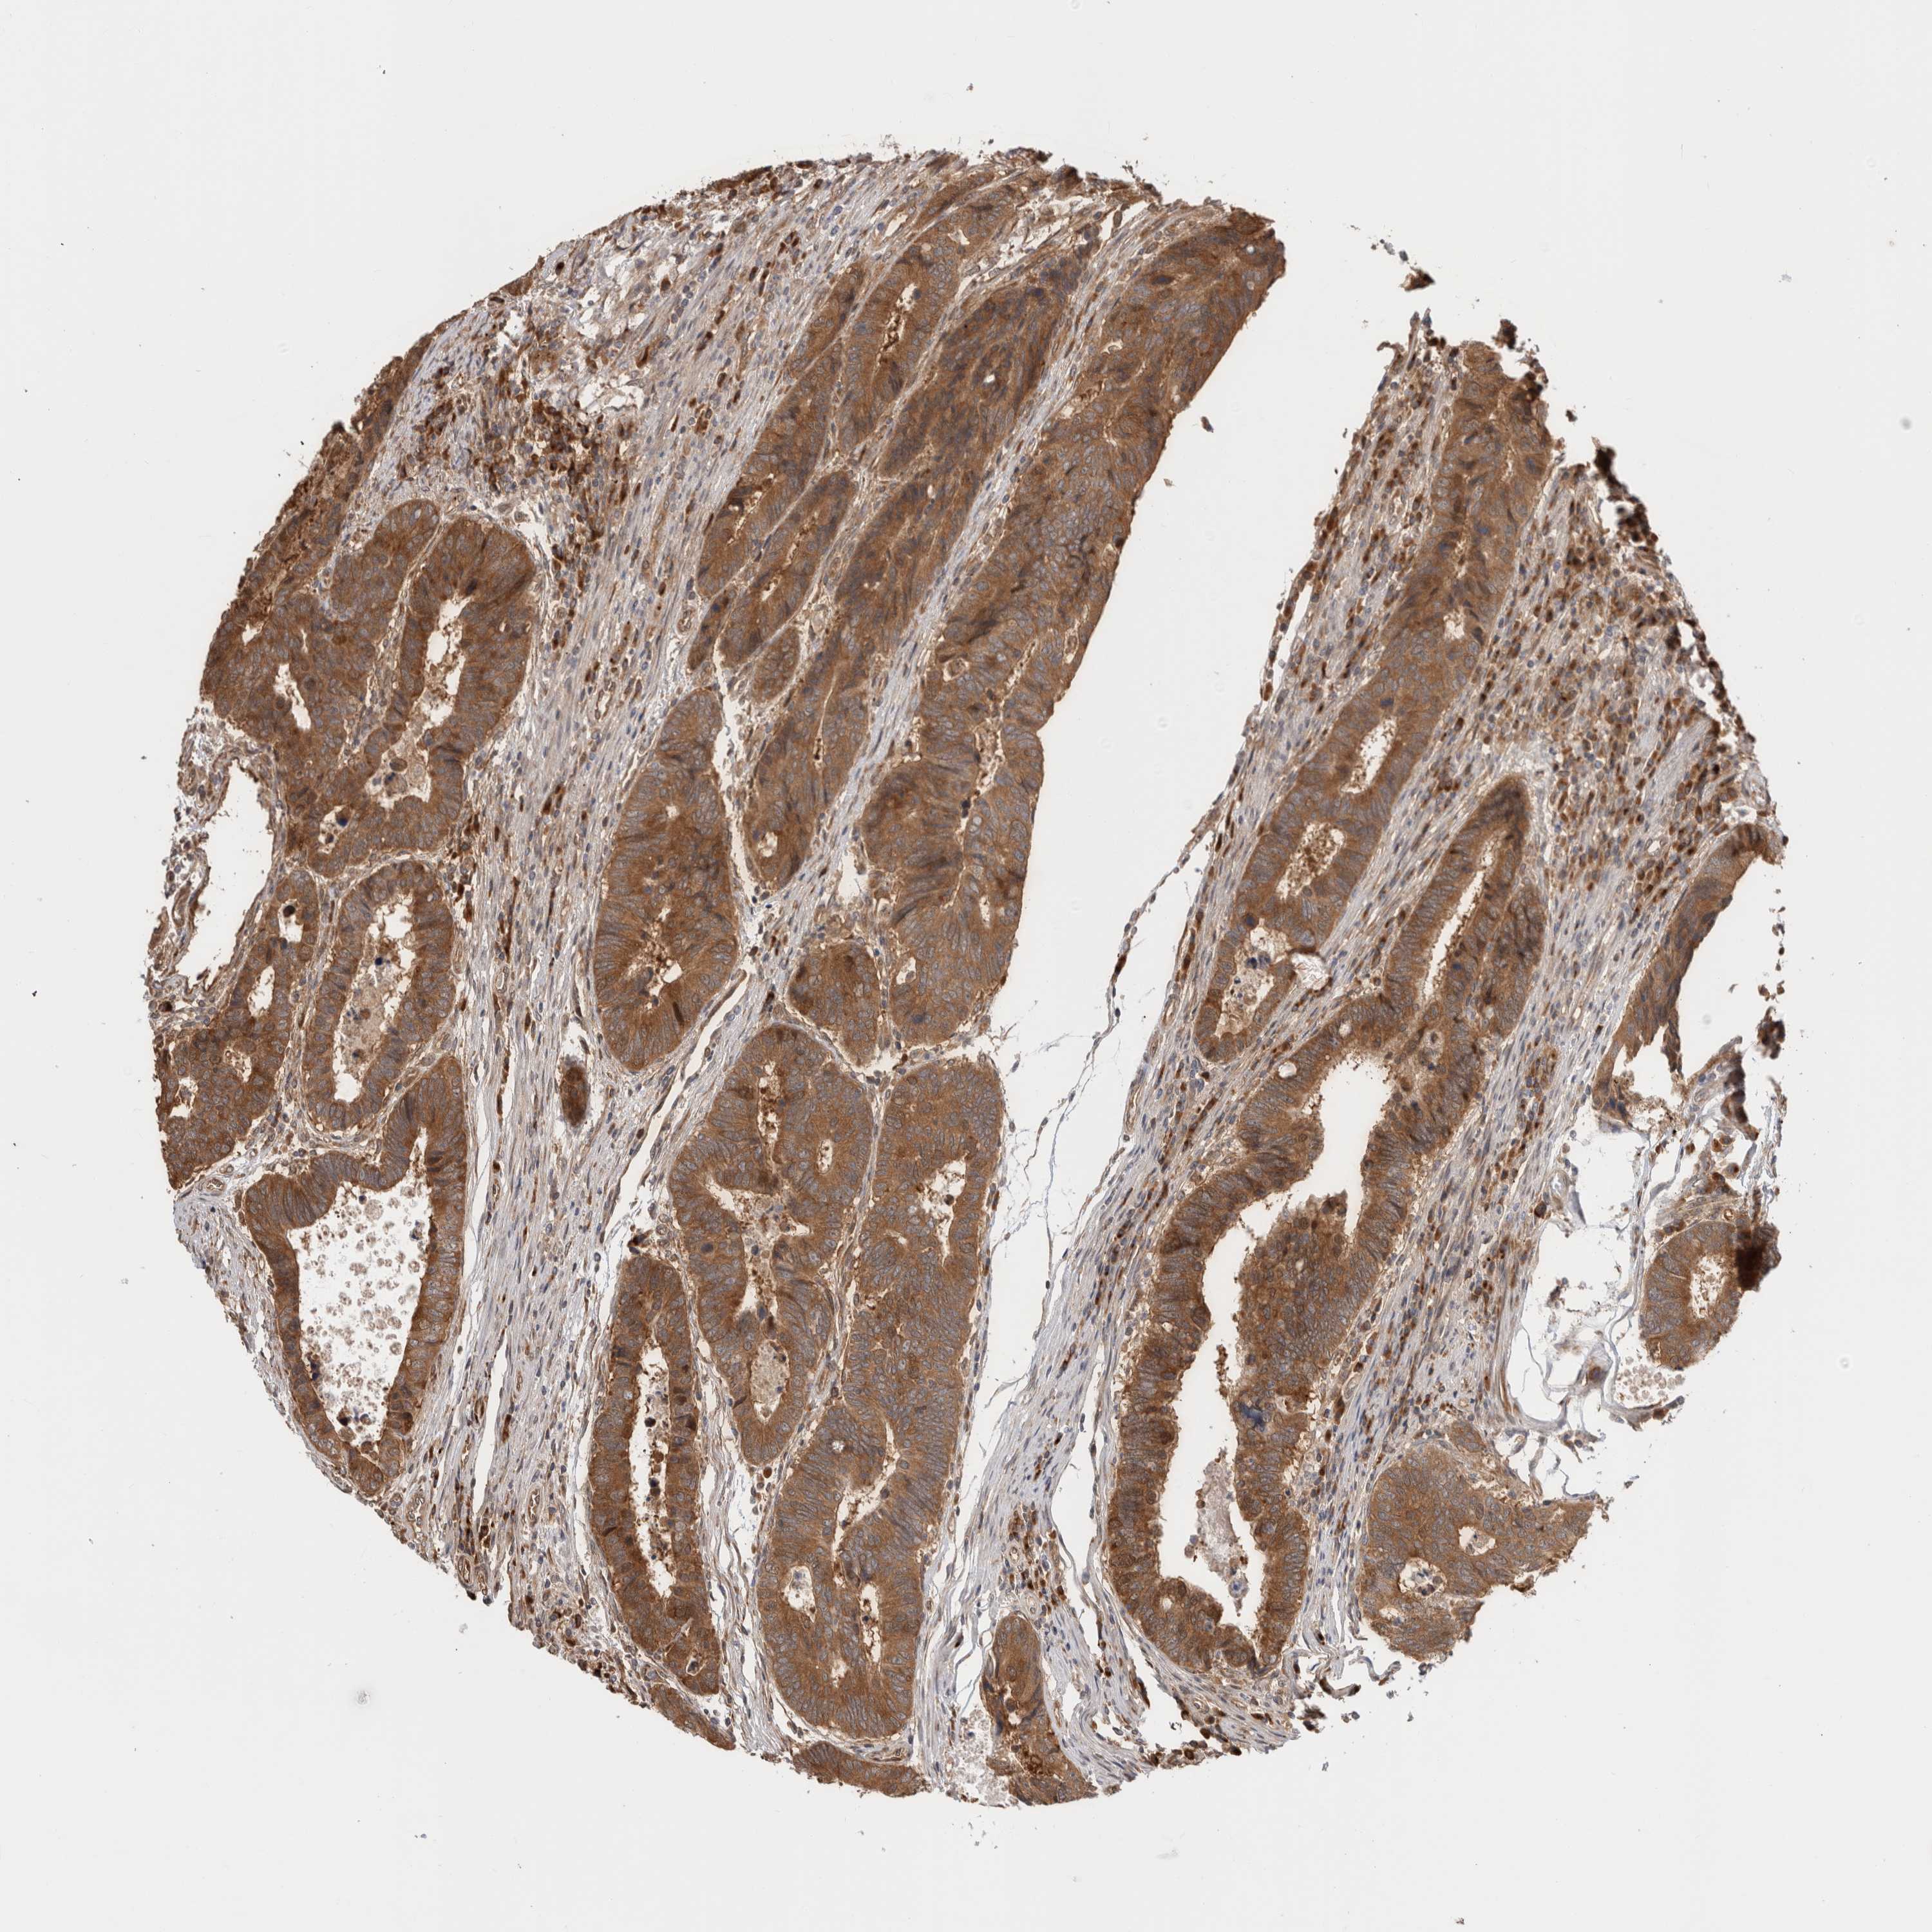

CANCER COLORECTAL CANCER Show tissue menu

Colorectal cancer

Human cancer

Colon adenocarcinoma